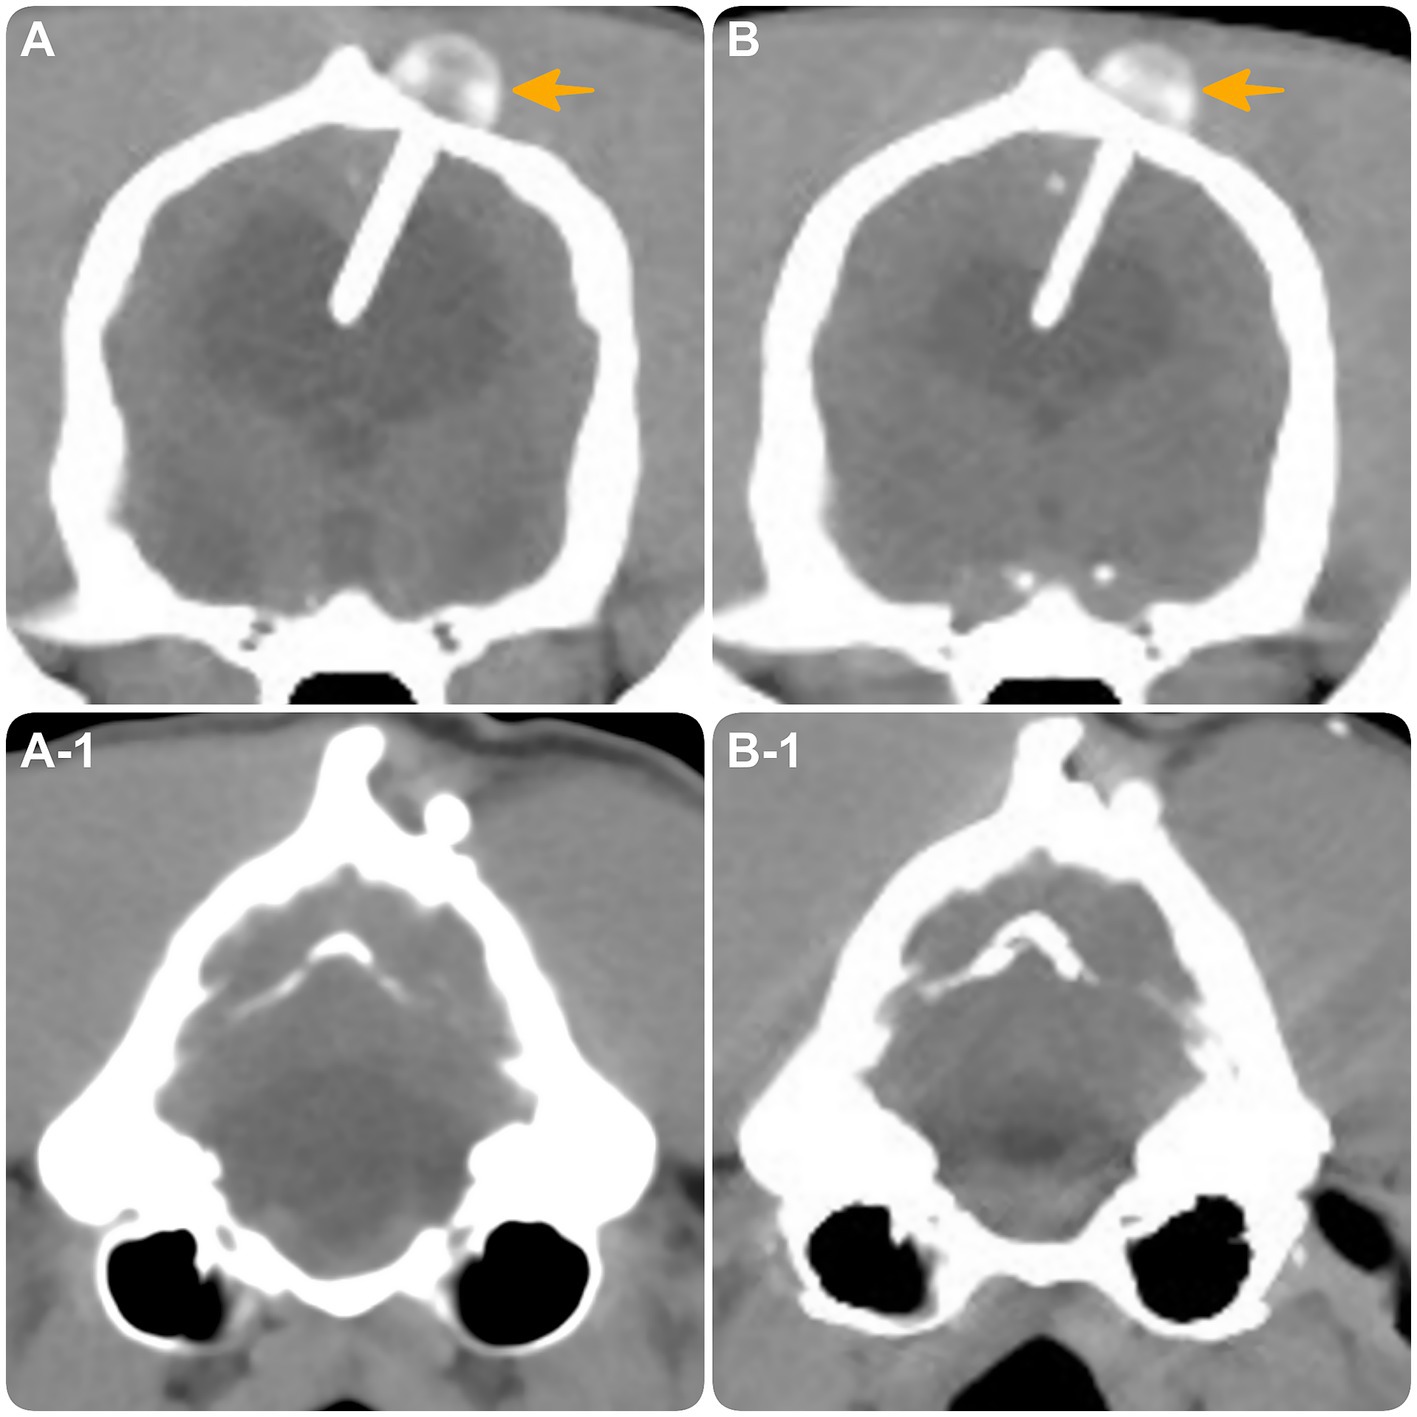

Figure 4. Transverse CT images at the level of the interthalamic adhesion (A,B) and the fourth ventricle (A1,B1). (A,A-1) obtained at the time of distal catheter fracture. (B,B-1) obtained 10 months post-revision surgery, demonstrating intact shunt positioning (yellow arrow) with moderate reduction in hydrocephalus and expansion of brain parenchyma.

A CT scan was performed to assess shunt integrity and positioning. Findings indicated undershunting due to fracture of the distal catheter at its anchoring site in the abdominal wall (Figure 3A). Despite the extra catheter length, the patient’s weight increase from 25 to 42 kg, combined with firm fixation to both the abdominal musculature and parietal peritoneum (12, 26, 27), likely resulted in mechanical strain, leading to catheter fracture. During revision surgery, the fractured distal catheter was trimmed and extended with a titanium connector, then re-anchored solely to the abdominal musculature to reduce mechanical stress and avoid recurrence. Shunt patency was confirmed intraoperatively, with CSF observed flowing from the proximal end of the distal catheter at the rupture site.

Three and a half months later, at 24 months of age and 10 months post-revision surgery, the dog was clinically unchanged (Supplementary Video 3). Repeat CT scan revealed no concerns with the VP shunt and demonstrated moderate reduction in hydrocephalus with noticeable brain parenchyma expansion compared to the CT at the time of catheter fracture (Figure 4).